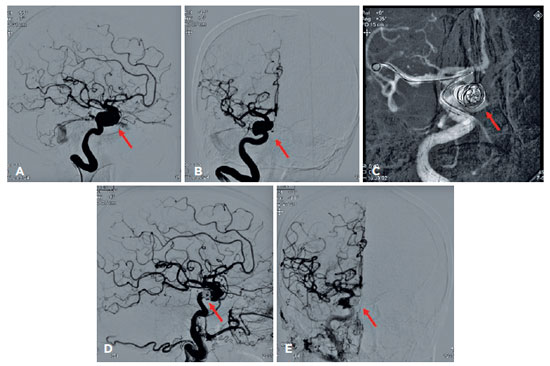

The patient received contrast tomography of the orbit, which revealed dilatation of the superior ophthalmic vein, while arteriography revealing a ruptured saccular aneurysm in the intracavernous portion of the right internal carotid that induced an arteriovenous fistula of the CS (Figure 3A-B). Together with the Neurology and Interventionist Radiology team, it was decided to perform endovascular closure of the fistula (Figure 3C). Anomalous communication was successfully treated (Figure 3D-E), which reduced the eyelid edema and chemosis (Figure 4). Even with treatment, however, corneal edema, hyphema, and vitreous hemorrhage were (4+/4+) on ocular ultrasound, and RE UCVA decreased to near complete absence of light perception. At a 3-month follow-up examination, there was partial improvement of corneal edema and hyphema but no improvement in VA.

11-fig03tb.jpg)